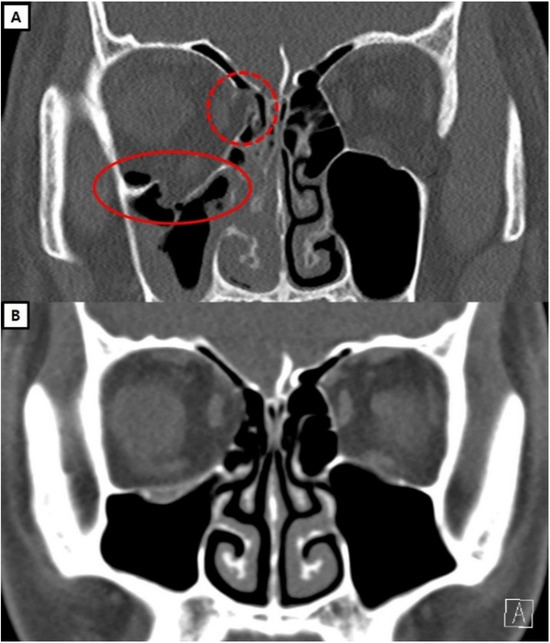

Representative Cases